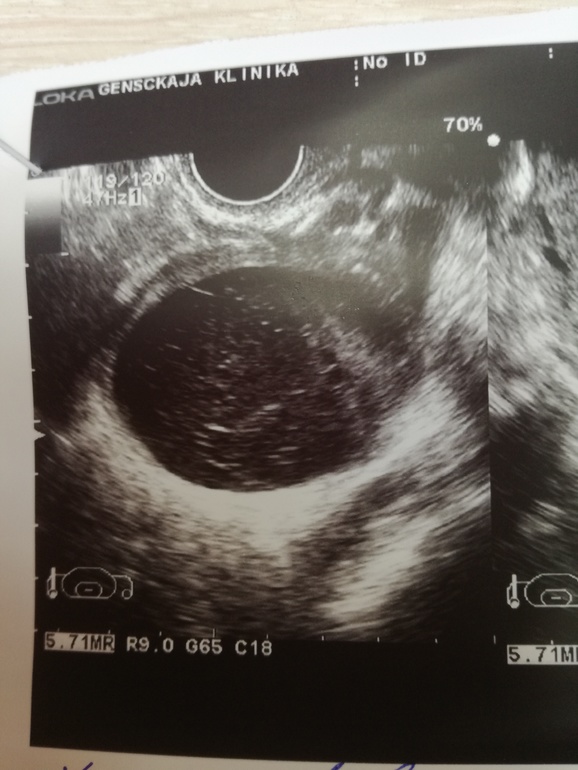

У меня такая же в прошлом цикле была. Судя по краям фолликулярная киста это.

Четкие и ровные края, да?

да, при кисте ЖТ края вообще не ровные, а тут как шарик.

Этот вопрос бы решило узи с ЦДК. Если есть кровоток, то ЖТ, если нет - то киста фолликула. Ровные края, черный цвет - это классически фолликул

ЦДК - Цветовое доплеровское картирование. На нём видно кровотоки, вокруг ЖТ должно быть "огненное" кольцо Надежда есть всегда)

Судя по фото скорей фолликулярная, края ровные и содержимое . Думаю О или не было или могла быть в Л Я так как на 18 дц там была киста и ее теперь нет, значит там мог быть тоже фоллик который лопнул.

это фолликулярная киста. у кисты Жт более рваные края и более четкие взвеси